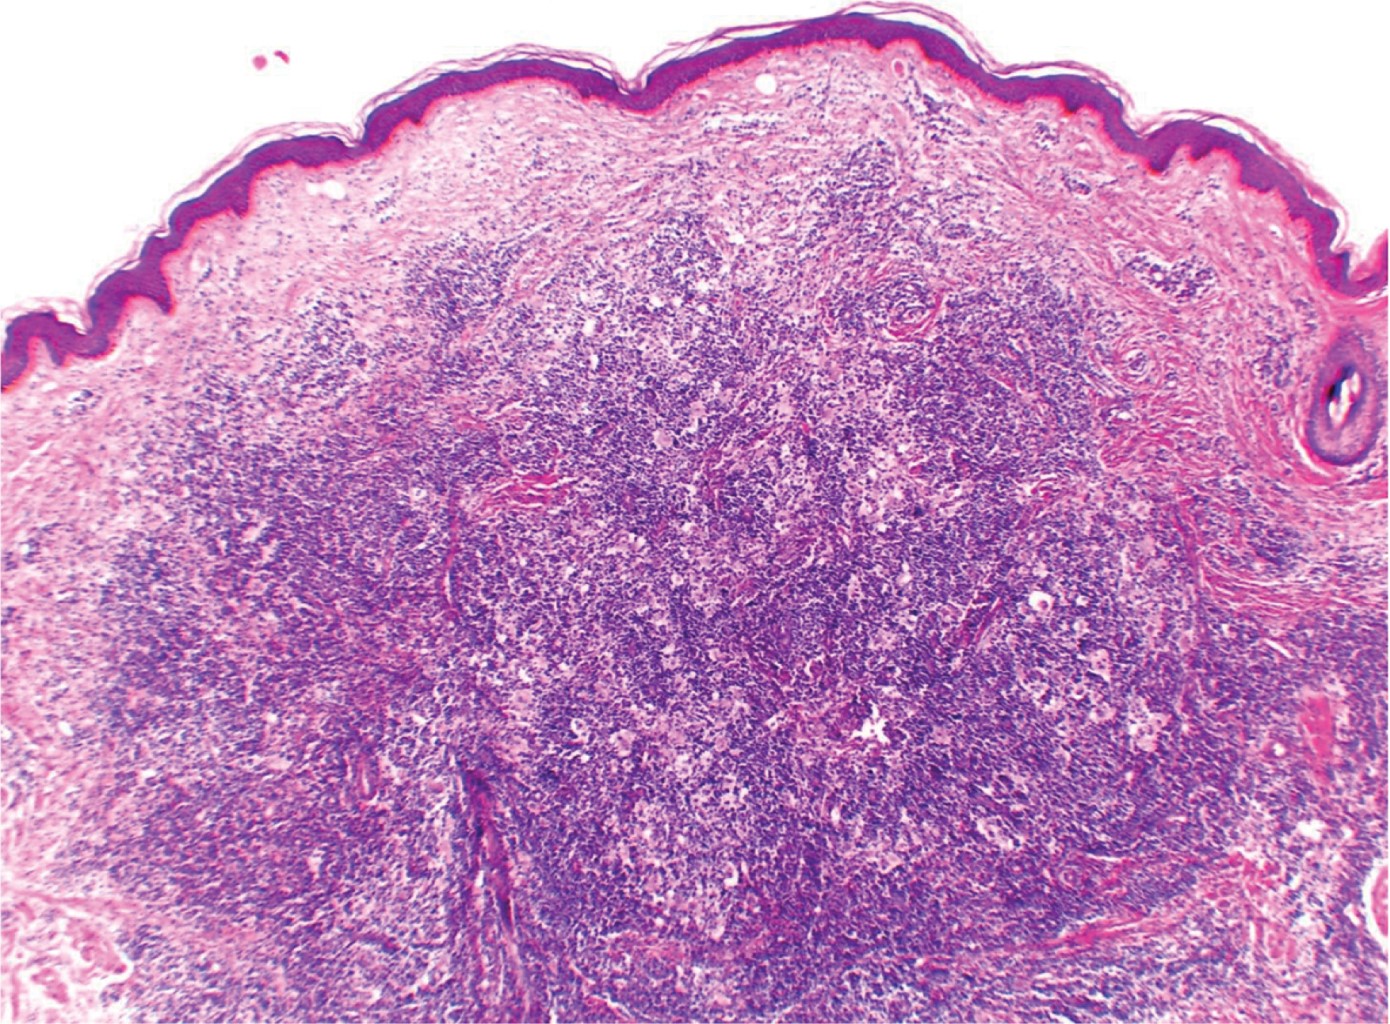

Cutaneous sinus histiocytosis. Clinicopathological study of 33 patients at the Centro Dermatólogico Pascua

Cutaneous sinus histiocytosis, emperipolesis, Rosai-Dorfman disease.

Introduction: Cutaneous sinus histiocytosis (CSH) is a clinical form of Rosai-Dorfman disease or sinus histiocytosis with massive lymphadenopathy (SHLM), this variety limited to the skin is considered rare. Objective: To know the epidemiology and clinical-pathological characteristics of this entity in the Centro Dermatológico "Dr. Ladislao de la Pascua" (CDP) in Mexico City. Material and methods: A retrospective, cross-sectional, descriptive and observational study was performed with the records of the CDP Dermatopathology department in 34 years (1985-2019). Cases with histological diagnosis of sinus histiocytosis and only cutaneous disease (by clinical data) where selected. Results: A total of 33 cases were found, the female gender predominated in 24; the age was between nine and 90 years, with a median of 36. The most frequent location was the face, the clinical aspect was diverse; most cases were chronic and with an asymptomatic evolution. Histologically, the image was characteristic, emperipolesis was observed in all cases. Conclusions: Cutaneous sinus histiocytosis (CSH) is not as rare as was previously thought, we consider that its recently increase in diagnosis relies on greater clinical and histological knowledge of this disease, hence our interest in communicating this series of cases.

Figure 1